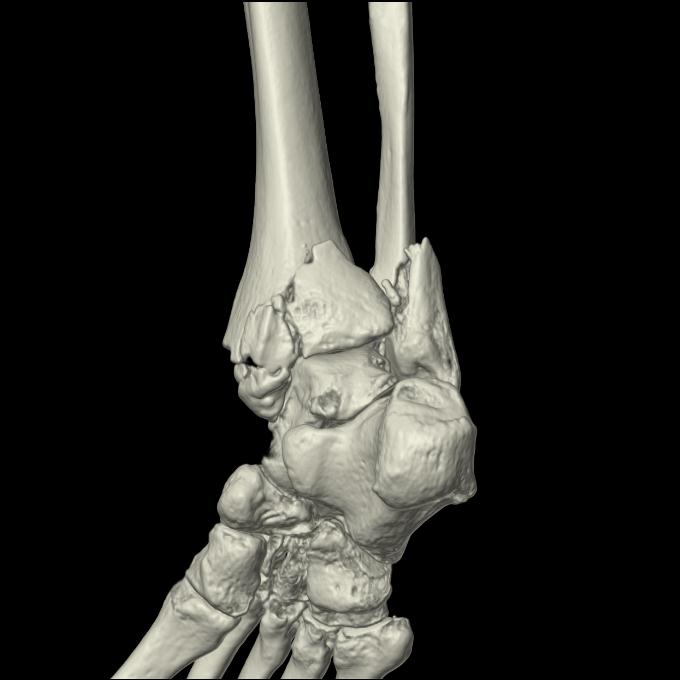

102755 1/4 2R 1/15 2R 右足関節 68歳女性 右三果脱臼骨折